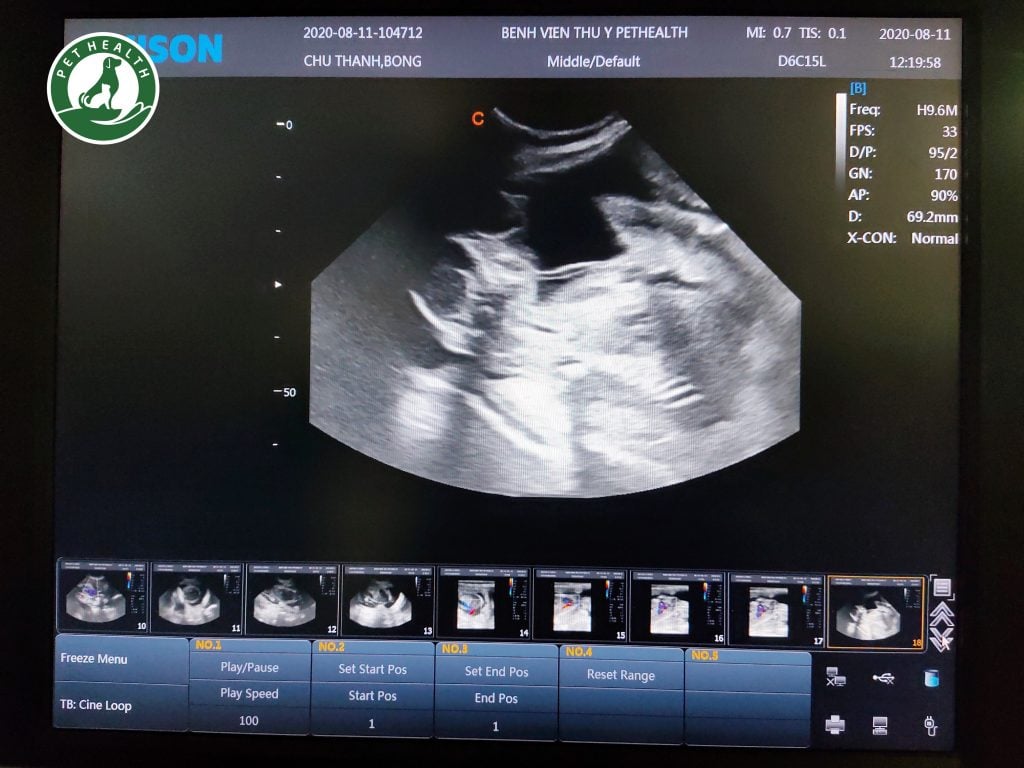

Siêu âm thai cho chó là một kỹ thuật hiện đại vô cùng hữu ích và an toàn. Nếu bạn chưa biết phải ra quyết định như thế nào để đưa chó của mình đến cơ sở thú y siêu âm thai thì chúng tôi sẽ đưa ra cho bạn những gợi ý rất hứu ích mà bạn cần xem xét như sau

Thời điểm nào là thích hợp để siêu âm thai cho chó?

Trên lý thuyết, túi ối có thể được phát hiện khi thai được 20 ngày tuổi. Nhưng điều này sẽ đúng với các giống chó có kích thước lớn. Trọng lượng khi trưởng thành > 30kg. Đa phần các giống chó trung bình và nhỏ sẽ nên đi siêu âm lần đầu vào ngày thứ 30 sau ngày phối cuối cùng.

Trên thực tế, việc kết hợp giữa tinh trùng và trứng không phải lúc nào cũng xảy ra đúng vào ngày phối giống. Nó có thể diễn ra sau việc phối giống 3-4 ngày. Khoảng thời gian 30 ngày sau ngày phối gần nhất là một thời điểm hiệu quả với hầu hết các trường hợp mang thai. Lúc này bác sĩ có thể xác định các thông tin sau:

- Số lượng con trong lứa đẻ (chưa cố định, giai đoạn cuối vẫn có thể có sự thay đổi do một vài vấn đề)

- Tần số tim thai

- Tính chất nước ối

- Một số bệnh lý bẩm sinh

Siêu âm lần 2

Tuy chỉ mang thai có 60 -62 ngày, nhưng những biến đổi của thai hoàn toàn có thể diễn ra rất nhanh. Việc siêu âm thai lần 2 trong thai kỳ rất hữu ích, chúng tôi sẽ thực hiện siêu âm lần 2 vào thời điểm 55 ngày sau phối.

Để siêu âm xác định số lượng thai và các dấu hiệu sinh tồn của thai, các máy siêu âm đơn giản và đầu dò Micro Convex có thể làm rất tốt điều này.

Trong những trường hợp đánh giá bệnh lý phức tạp, bác sĩ sẽ lựa chọn giúp bạn 1 máy siêu âm có khả năng đáp ứng các kỹ thuật cao hơn như: sử dụng đầu dò Liner, phần mềm Doppler…